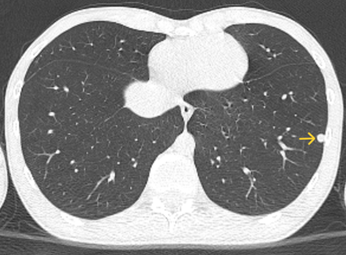

- CLVT lồng ngực không tiêm thuốc cản quang: Phổi phải: thùy giữa có nốt đặc nhỏ đường kính khoảng 2mm, bờ đều. Phổi trái: phân thùy lưỡi, thùy dưới có nốt đặc đường kính lần lượt là ~ 2mm và 6mm, bờ đều.

Hình 4: Hình ảnh chụp CT lồng ngực nốt đặc ở thùy dưới phổi trái (mũi tên vàng)